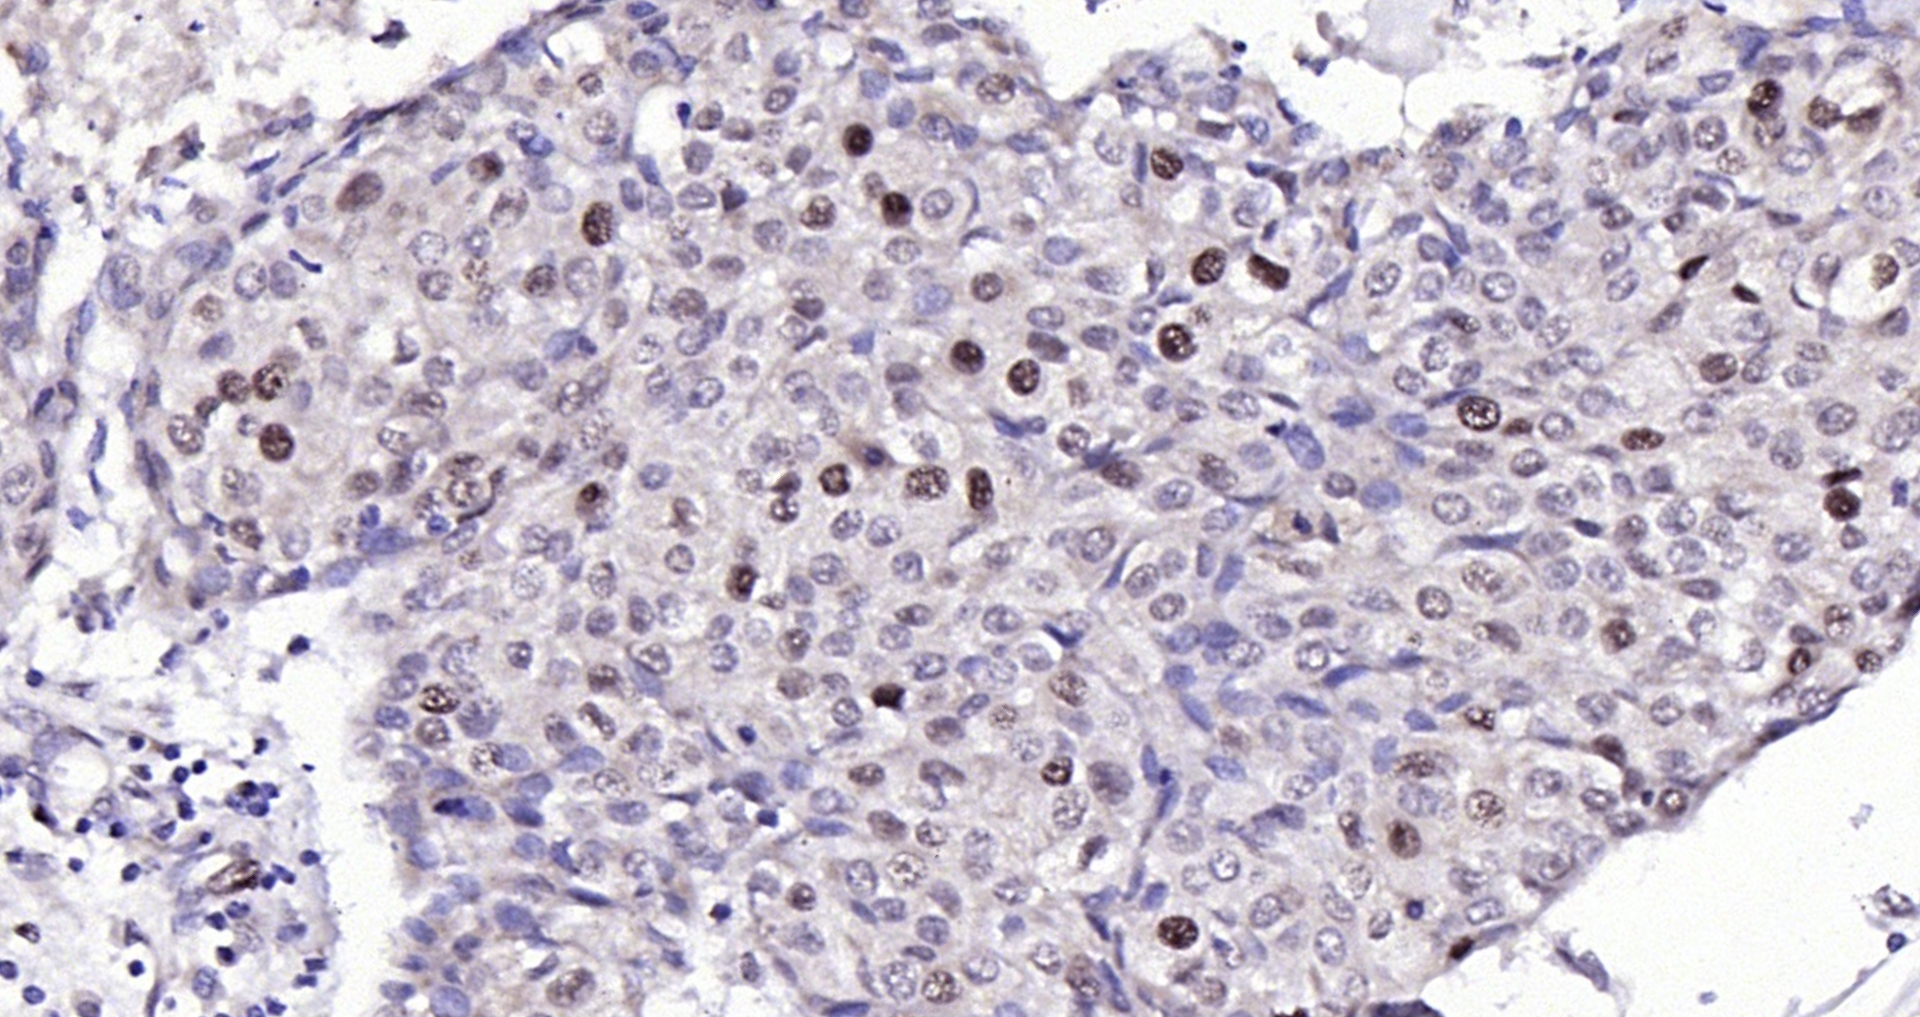

• IHC-P

IHC-P 1:200-400